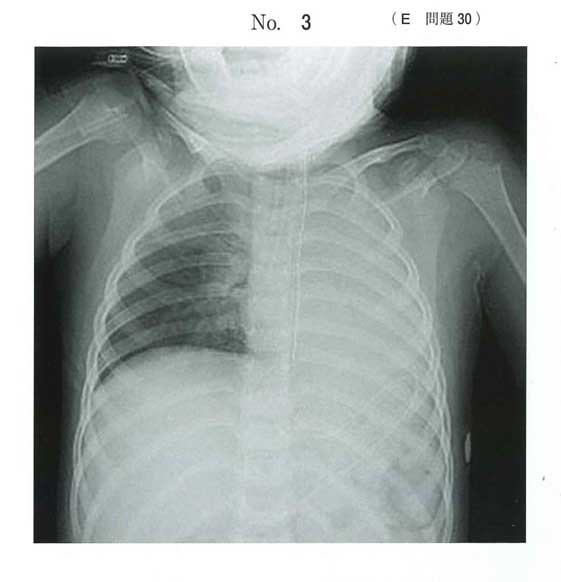

チューブが片側主気管支に入り込んでいて片肺挿管

左肺真っ白